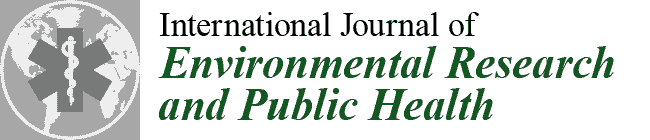

2.2. Raman Microspectroscopy

3.1. Detected Compounds

| M2 | m | 38 | N | programmer (O) | CaCO3, Fe3O4, TiO2-A, TiO2-R | 1 |